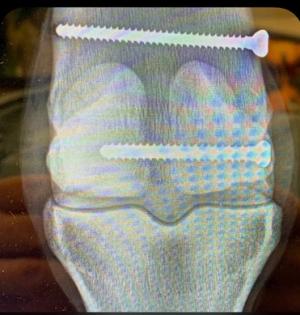

According to Bloodhorse, “the injury was diagnosed after the 3-year-old colt worked a half-mile Thursday (May 28) in :48 4/5 at Santa Anita Park for trainer Bob Baffert. He went into surgery at the equine hospital at the Southern California track, Bolton said.” Two screws were inserted (see X-ray), and the colt will remain at Santa Anita for the early part of his post-surgery recovery. Bolton said the horse has been withdrawn from Derby contention and is now being retired to stand at stud.